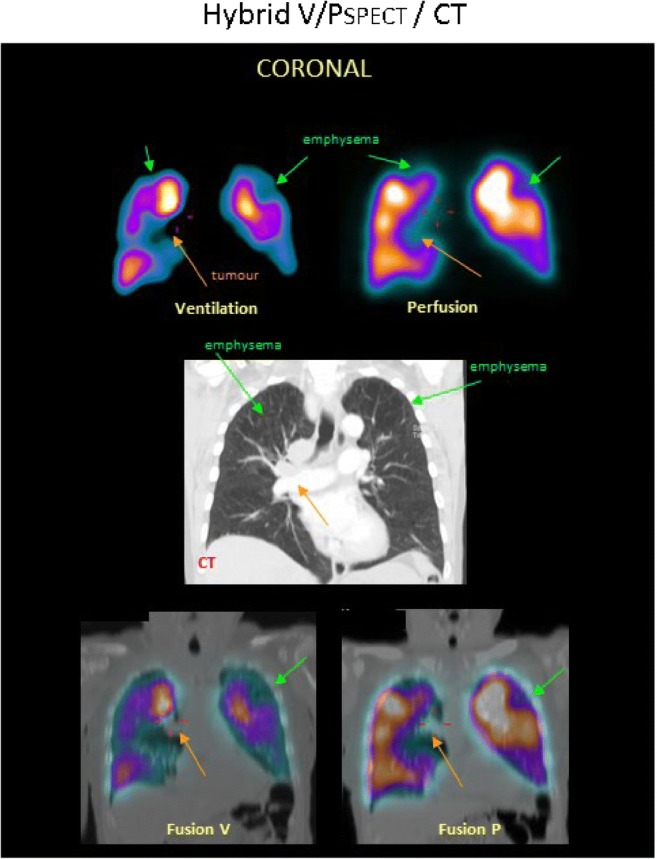

L’acquisizione ibrida SPECT/CT rappresenta lo stato dell’arte. Una scansione CT a bassa dose viene eseguita sequenzialmente alla SPECT. Questa componente anatomica non solo serve per la correzione dell’attenuazione, ma fornisce informazioni cruciali per la diagnosi differenziale: un difetto di perfusione può essere correlato ad una polmonite, un versamento pleurico o un’area di enfisema visibili alla CT, riducendo drasticamente i falsi positivi per embolia polmonare.

Paziente con BPCO, enfisema e tumore. Le sezioni coronali mostrano una distribuzione disomogenea della ventilazione con un pattern di deposizione di 99mTc-Technegas® tipico della BPCO. La perfusione segue il pattern della ventilazione. Si osservano difetti concordanti di ventilazione e perfusione in entrambi i lobi superiori (frecce verdi) e a destra del mediastino (frecce arancioni). Nella fila centrale della corrispondente sezione TC coronale, si osserva enfisema in entrambi i lobi superiori (frecce verdi), così come un tumore nel mediastino (freccia arancione). Sono mostrate le immagini di fusione tra TC e SPECT di ventilazione, e tra TC e SPECT di perfusione.